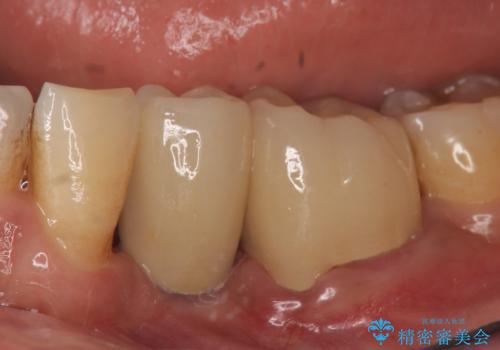

インプラント 左下奥歯の咬み合わせの改善

左下6も再根管治療後、オールセラミッククラウンによる補綴を行いました。

オールセラミッククラウンについて

今回用いたオールセラミッククラウンはジルコニアフレームという白い素材の上にセラミックを盛っているため、審美性が非常に高いのが特徴です。

また、ジルコニアは人工ダイヤモンドの材料にも使われているほど高い強度を持っており、そのためオールセラミッククラウンは審美性だけでなく、奥歯やブリッジの補綴も可能とするクラウンです。